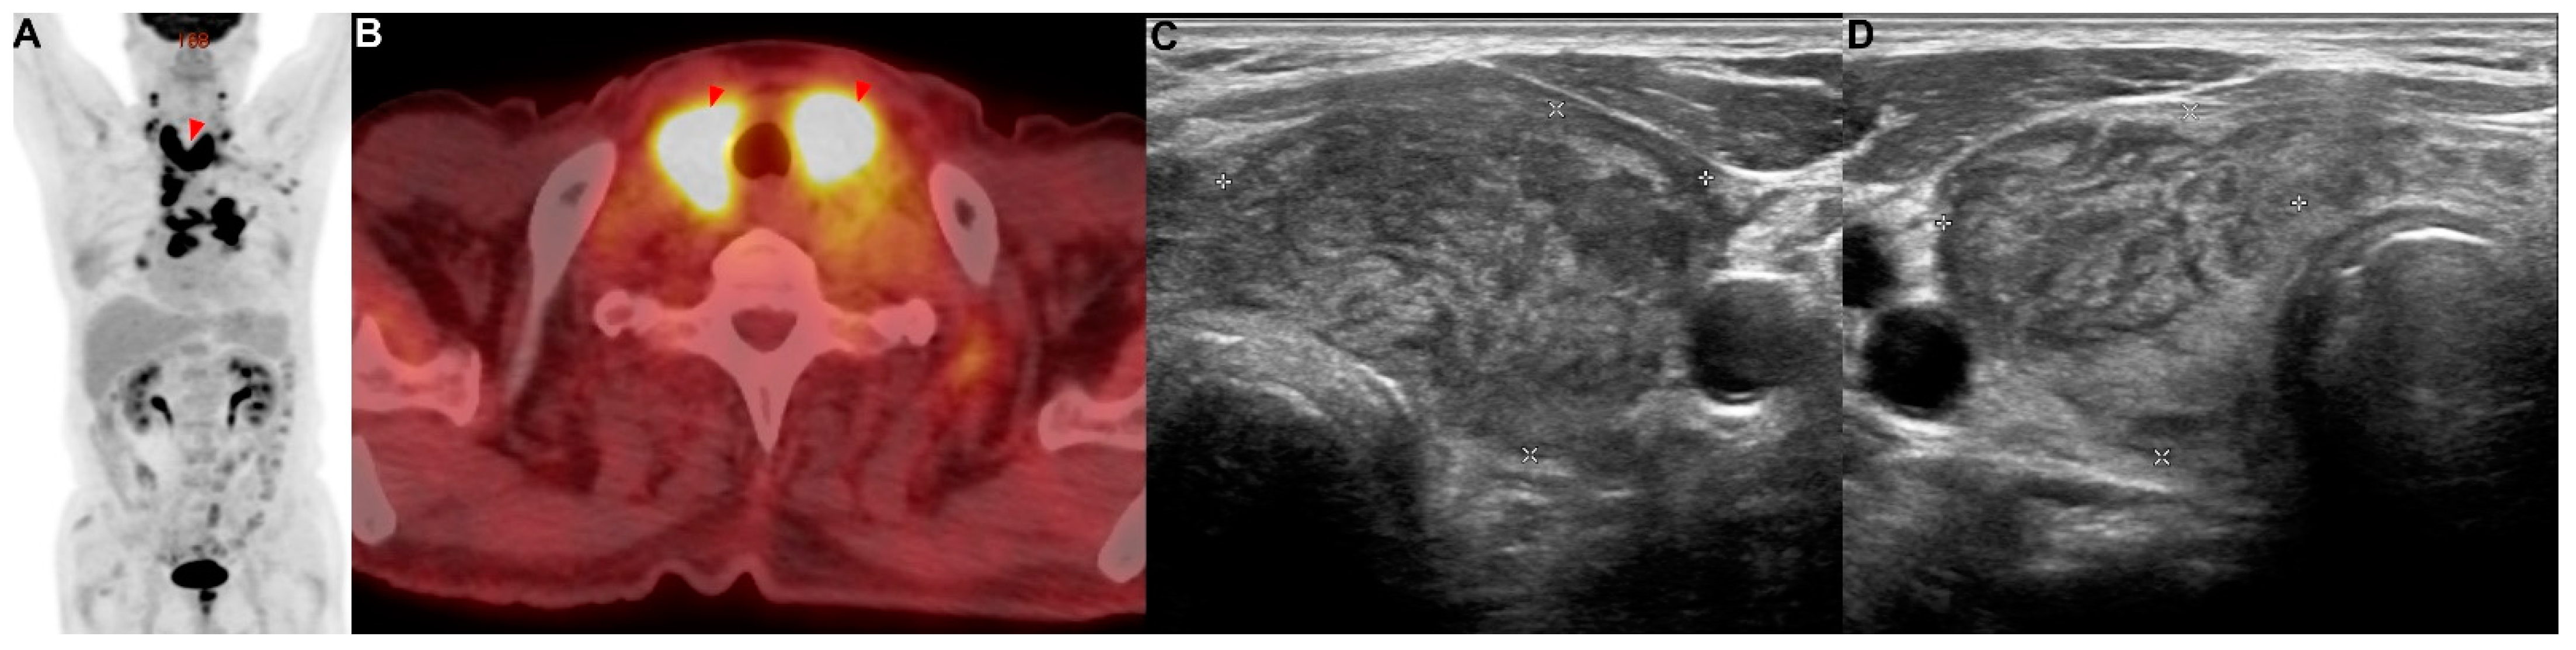

A 71-year-old man presented with a 2-week history of progressive dyspnea and chest discomfort. He had a history of 30 pack years of smoking and underwent surgery for cerebral hemorrhage 7 years ago. He stated that he did not take any medications or have other illnesses, including cardiovascular, allergic, rheumatic, or respiratory conditions. A contrast-enhanced computed tomography (CT) scan of his chest showed a lung mass invading the lobar bronchus of the right middle lobe. A bronchoscopic biopsy was performed, and poorly differentiated NSCLC was diagnosed. If there was no metastasis, the tumor was considered stage IIIB as T4N2. There was no suspicious finding of distant metastasis except for a hypermetabolic lesion (SUVmax = 4.76) of the pancreas tail, which was observed using positron emission tomography/computed tomography (PET/CT) (Figure 1A–C). Aspiration cytology was performed from the lesion of the pancreas tail through endoscopic ultrasound-fine needle aspiration (EUS-FNA) (Figure 1D). As a result of the cytological examination, a poorly differentiated non-small-cell carcinoma with the same morphology as the cancer cells in the lung cancer tissue was confirmed in the aspirated specimen (Figure A1A). This patient was treated with six courses of platinum-based chemotherapy (gemcitabine and cisplatin) for stage IV NSCLC.

Figure 1. Patient 1: a 71-year-old man diagnosed with non-small-cell lung cancer (NSCLC) with a solitary metastasis in the tail of the pancreas. (AC) Positron emission tomography/computed tomography (PET/CT) showed a solitary metastatic lesion (red arrowhead) in the tail of the pancreas. (D) EUS-FNA was performed at the metastatic lesion (red arrowhead) in the pancreas.